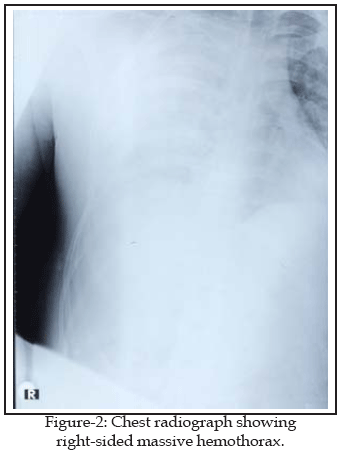

Six hours after the admission, the patient became acutely hypotensive with associated tachycardia and tachypnea. A repeated chest radiograph revealed massive hemothorax (Fig-2). A right tube thoracostomy was performed. Approximately 1800 ml of blood was evacuated. The tube was occluded with a clamp and he was immediately taken to the operating room and intubated. A right anterolateral thoracotomy was performed through the fifth intercostal space and a large amount of clot was evacuated. We discovered that right lung was adhesive to the mediastinum and diaphragma. The lung was separated from these adhesions by blunt and sharp dissection. After pulling back the lung, we found a large compressive hematoma infiltrating the mediastinum. When this hematoma was removed, a massive caval bleeding was discovered. Digital control was established. The pericardium was opened due to a pericardial laceration. However, myocardium was intact. Two longitudinal tears were identified at the anterior and posterior walls of the SCV (approximately 1.5 cm in lengths). The tip of central jugular venous line was found to be situated in the mediastinum through caval rupture. It was removed by anesthesist.